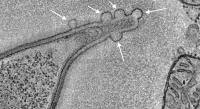

Friendly messages. Vesicles (arrows) carry chemical cargo from a friendly bacterium through a host's intestinal cell to immune cells on the other side of the cell. Image: Ivaylo Ivanov / Columbia University Vagelos College of Physicians and Surgeons.

The 3D images revealed that once bacteria hook into a cell in the gut lining, the cell swallows certain proteins from the bacteria and bundles them into tiny sacks. The sacks are transported through the cell to the tissue side of the gut lining, where they activate Th17 immune cells.